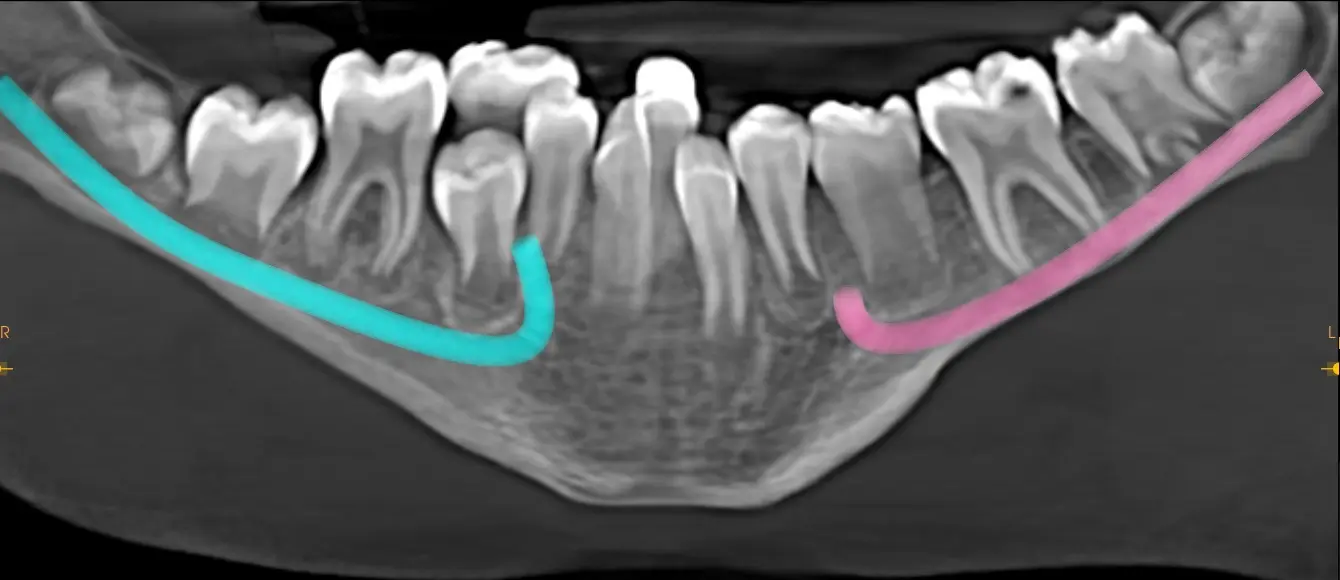

La paciente concurre a realizarse una telerradiografía de perfil con estudios cefalometricos para iniciar tratamiento de ortodoncia, 30 días después concurre nuevamente para realizarse una tomografía ya que la paciente relata que presenta el Síndrome de Pierre Robin, se logra observar un maxilar inferior de tamaño disminuido donde las piezas se encuentran apiñadas, el trastorno genera agenesia de los premolares en este caso piezas dentales 35 y 45 esta falta de espacio es una consecuencia común de la mandíbula pequeña (micrognatia).

En la Imagen Telerradiográfica se puede observar el poco desarrollo del cuerpo mandibular y el gonion.